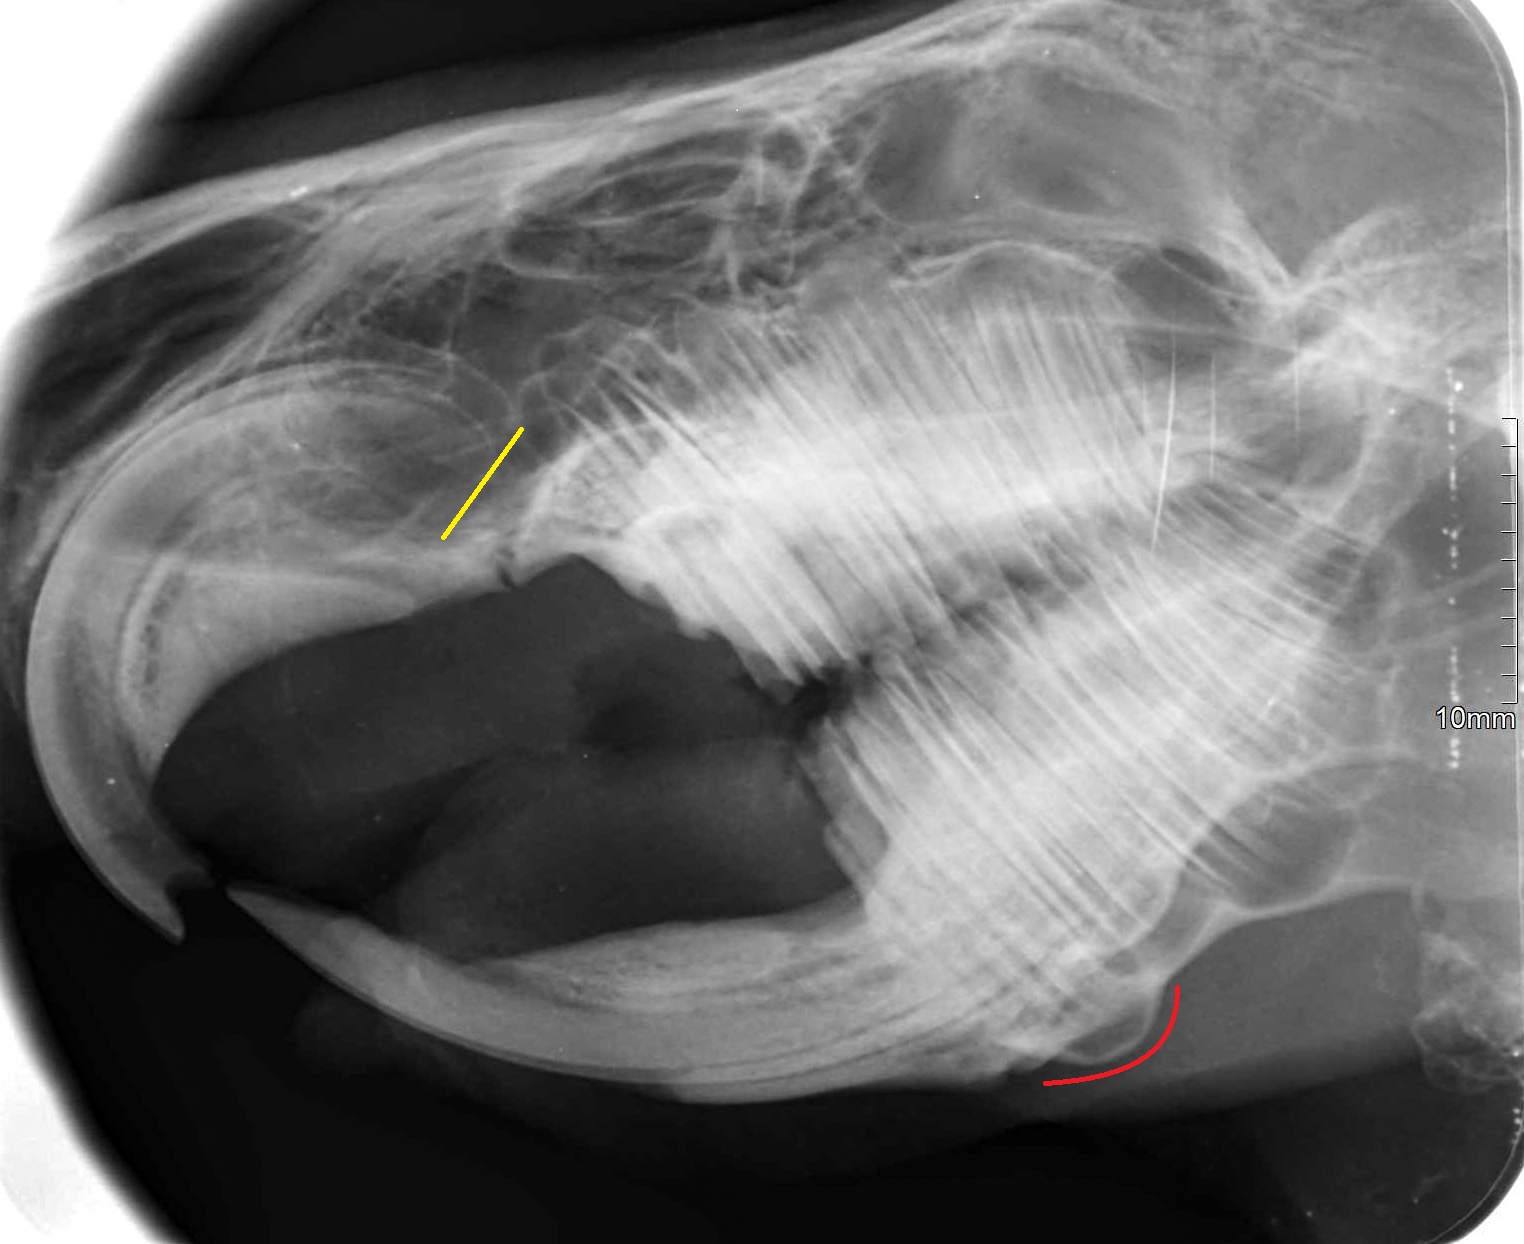

Za dvěma páry řezáků, které jsou vidět na první pohled, jsou v tlamičce schované ještě stoličky (správně premoláry a moláry) – a to čtyři na každé straně nahoře i dole. Všechny zuby morčete neustále dorůstají. Při normálním obrušování zubů vyrostou řezáky o 3 mm za týden, stoličky o 2–5 mm za měsíc. Pokud se zuby neobrušují, protože morčátko například nepřijímá potravu a je dokrmováno tekutou stravou, růst zubů se zpomaluje. Viditelná část spodních řezáků je obvykle třikrát delší, než viditelná část horních řezáků. Na bočním rentgenu vidíte, že velká část řezáků je ještě „schovaná“ v kosti. Spodní stoličky nerostou kolmo vzhůru, ale jsou nakloněny přes jazyk šikmo k sobě v úhlu asi 40°. Horní stoličky naopak míří mírně směrem ven do dásně pod tvářemi.

Žlutou barvou jsou vyznačeny konce kořenů řezáků, červenou barvou přerůstání kořenů stoliček v čelisti